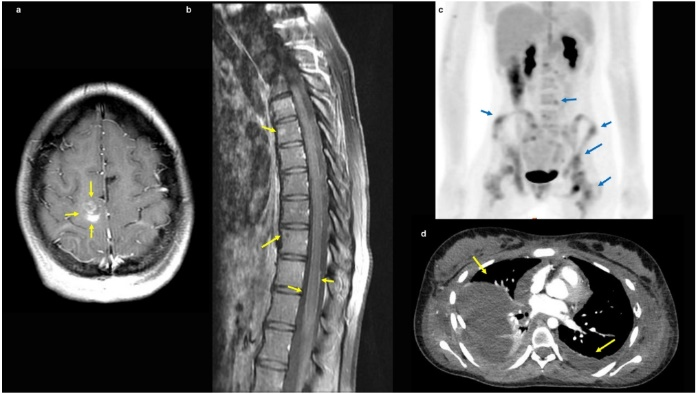

Schwartzentruber等首次报道儿童胶质母细胞瘤(GBM)的组蛋白H3F3A突变。然而,H3F3A突变型儿童高级别胶质瘤(pHGG)出现脑外转移的病理生理学以及临床特征和分子表型均未阐明。美国德克萨斯大学安德森癌症中心儿科护理部的Sana Mohiuddin等介绍一组H3F3A突变型pHGG弥漫性脑外转移病例的临床和分子特征,文章发表于2021年5月的《Journal of Clinical Neuroscience》在线。17岁女性,出现下肢无力伴复视三周。颅脑MRI显示右额强化病灶(图1a)。脊柱MRI提示胸椎和骨盆弥漫性增强和非增强的溶骨性病变以及软脑膜病变(LMD)(图1b)。髂骨病灶活检发现斑片状非典型细胞(表1)。重复骨髓活检结果为转移瘤p53蛋白阳性,ATRX阳性。6个月后,患者四肢剧烈疼痛再次入院;骨扫描为双侧股骨、左侧肱骨和右侧多根肋骨新发溶骨性病变(图1c)。患者接受双侧股骨和双侧髋骨的姑息性放疗(RT)。5个月后,转移至肺部,伴有明显的双侧胸腔积液(图1d)、胸壁肿块、盆腔软组织转移和双侧盆腔淋巴结肿大。盆腔软组织病变活检为胶质瘤转移(表1)。

图1. H3F3A-G34R突变型胶质瘤伴脑外转移的影像学特征。